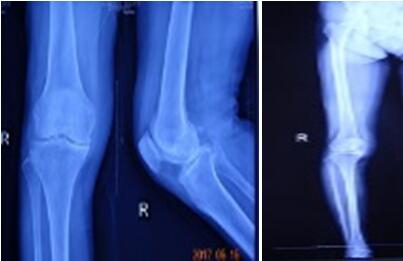

近日骨科在張富軍主任帶領(lǐng)下,在保膝理念的驅(qū)動(dòng)下,成功開(kāi)展我院首例生物單髁膝關(guān)節(jié)置換術(shù),更是全國(guó)第9例,西北地區(qū)第2例。這意味著本次手術(shù)在西安市內(nèi)乃至整個(gè)西北地區(qū)都極為罕見(jiàn),我院在骨關(guān)節(jié)病診治技術(shù)邁上了新的臺(tái)階,為膝關(guān)節(jié)炎患者提供了一種新的選擇。

提起膝關(guān)節(jié)置換術(shù),多數(shù)病人起初都是拒絕的,至少在單髁置換術(shù)出現(xiàn)之前,不乏有“談虎色變”的患者,而這些患者普遍遺留這樣一個(gè)問(wèn)題:能否僅置換部分磨損的關(guān)節(jié),保留大部分自體關(guān)節(jié),用更小的創(chuàng)傷解決痛苦呢?答案是肯定的,隨著科技的進(jìn)步和手術(shù)技術(shù)的精湛,單髁關(guān)節(jié)置換應(yīng)運(yùn)而生,成為近2年風(fēng)靡一時(shí)的手術(shù)方式,術(shù)中要求精確至1mm,其具有創(chuàng)傷小,恢復(fù)快,骨長(zhǎng)入理想,骨質(zhì)保留量大,本體感覺(jué)不破壞的優(yōu)勢(shì)。目前膝關(guān)節(jié)單髁置換多為骨水泥型,生物型全國(guó)僅開(kāi)展9例。生物型作為全新的置換方式比骨水泥型更具有突出的優(yōu)勢(shì),逐漸成為新的趨勢(shì)。